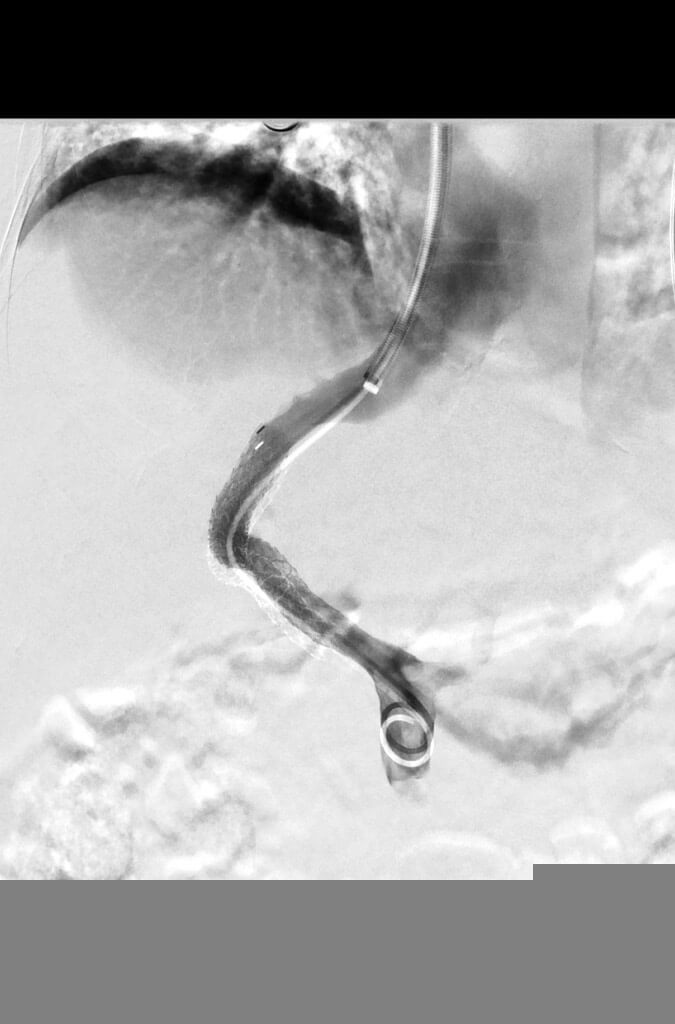

Tips Procedures

As liver disease progresses, it can result in increased pressures within the portal venous system (portal hypertension). Portal hypertension can lead to GI bleeding from varices (distended veins) or the development of ascites. A TIPS procedure can re-route blood flow through the liver in order to reduce portal venous pressure and reduce the likelihood of further bleeding from varices.